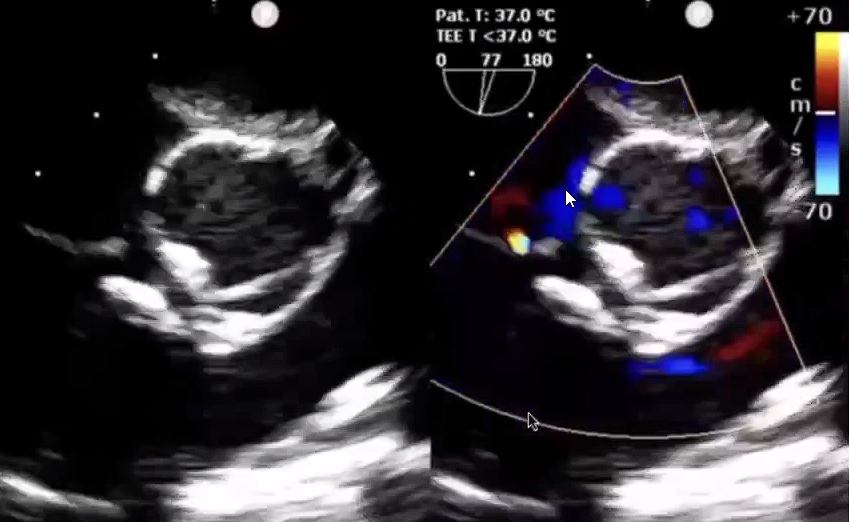

▲术后超声

在食道超声引导下,沿导引钢丝送入输送鞘管到左心室,撤除导引钢丝,经输送鞘置入一枚ABFDQ-II 06(封堵器腰高5mm×直径6mm)全降解封堵器进行封堵,推拉试验检测封堵器稳定性,食道超声检查无残余分流、对瓣膜无影响,封堵器形态、位置良好,遂释放封堵器,剪断并抽出成型线,撤出导管。术后超声示封堵效果十分理想,无残余分流、手术完成。

▲术前超声